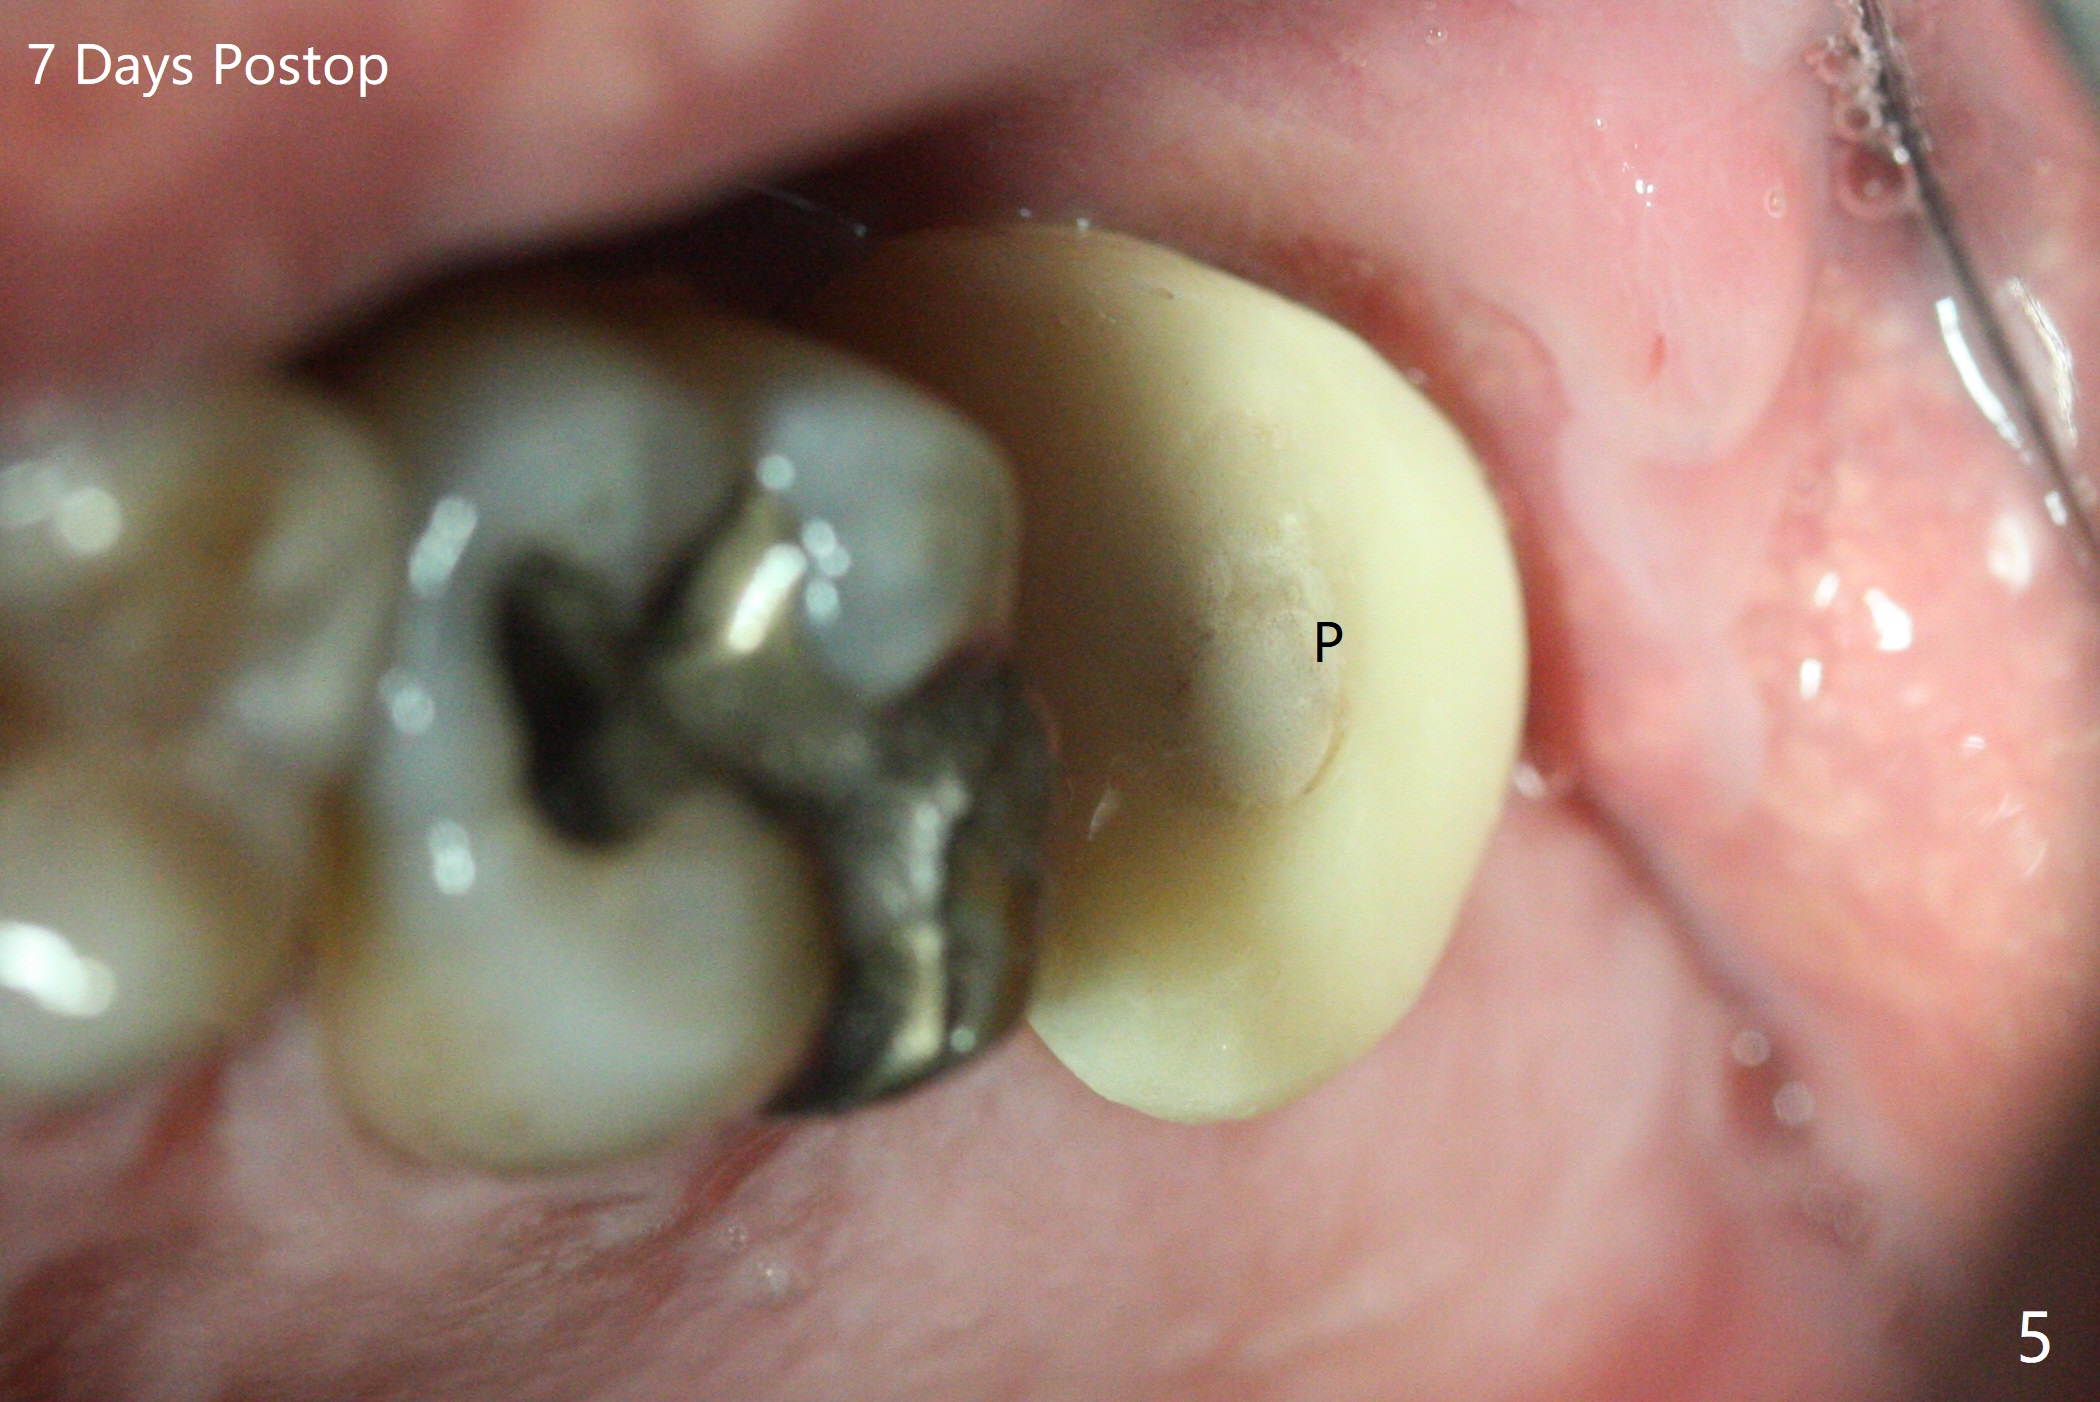

Designed osteotomy depth is 7.3 mm IS drill with 4 rings at #15. In fact osteotomy is created using 2.2 mm drill with 2 rings (sinus membrane barely visible from the osteotomy) and 3-4 mm ones with 3 rings. With an amalgam carrier of bone graft, sinus lift is initiated with 4x9 mm dummy implant (Fig.1). After loaded with totally 5 amalgam carriers of bone graft repeatedly with the 4x9 mm dummy implant, a 5x9 mm implant is placed with ~ 25 Ncm. After insertion of a 6x4(2) mm abutment, sticky bone cut into pieces (Fig.2) is inserted to peri implant space (Fig.3 *), followed by PRF and an immediate provisional. The latter dislodges 7 days postop; the socket starts to heal (Fig.4); the bone graft seems to be fixed in place. The provisional is reseated (no cement, Fig.5) without fear of its dislodgement again. The patient returns for cleaning 1 year 7 months postop (Fig.6,7). The socket heals, while the abutment is incompletely seated (Fig.7 <). Percussion at #18 disappears post RCT, whereas periapical radiolucency appears post RCT (compare Fig.8,9). When the 6x4(2) mm incompletely seated abutment is removed, the implant well is dirty. The smaller abutment with longer cuff is seated fully (Fig.10).